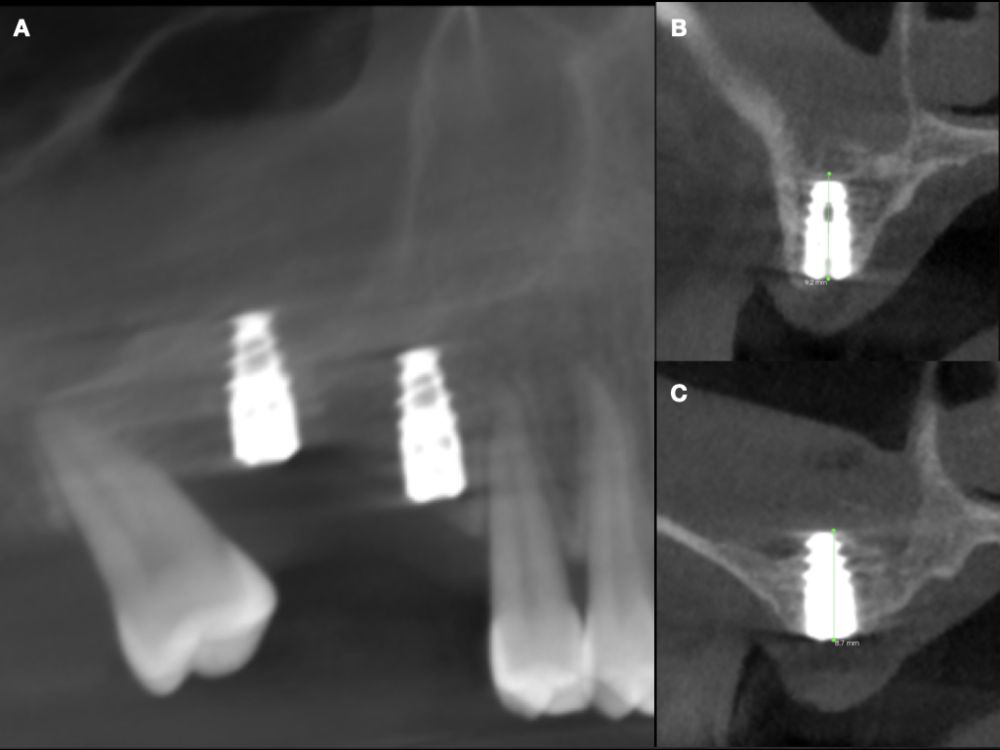

Seis meses tras la cirugía de elevación de seno maxilar se realizó la reentrada para la colocación de implantes. Se obtuvo una biopsia de tejido óseo de 3 x 7 mm mediante trefina y se solicitó un análisis histomorfométrico, obteniendo un 30,56% de hueso vital (Figura 7). Tras la muestra para la biopsia se colocaron dos implantes bone level Naturactis de ETK® (ETK Implants S.L, Sant Boi de Llobregat, España) con un torque de inserción de 35 Ncm, comprobándose su correcta colocación en el postoperatorio inmediato mediante una radiografía periapical (Figura 8). Seis meses tras la colocación de los implantes la paciente pudo acudir a realizarse la segunda fase para colocar pilares de cicatrización, y mediante un CBCT de comprobación se valoró la altura ósea final, teniendo un incremento de 4,2 mm en la zona del 1.6, y de 6,1 mm en la zona del 1.7 (Figura 9).